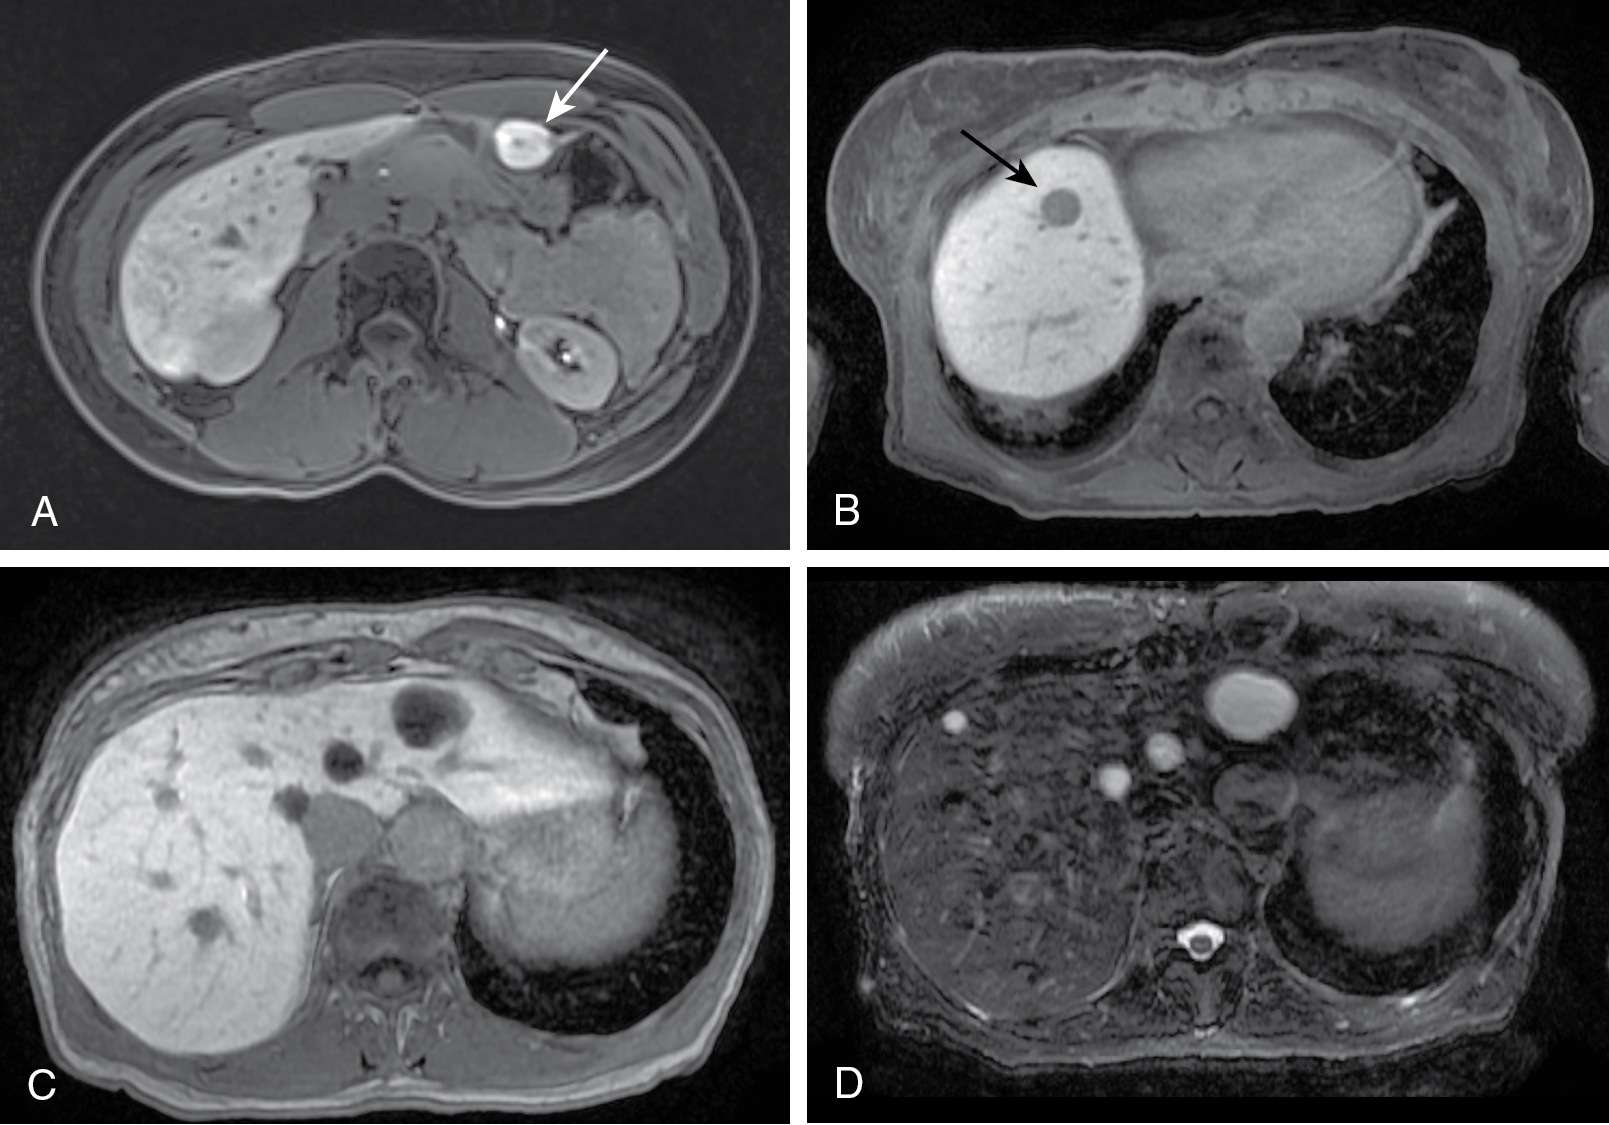

در میان ضایعات بدخیم کبد، کارسینوم هپاتوسلولار (HCC) شایعترین نوع سرطان اولیه کبد است که اغلب در بیماران مبتلا به سیروز یا عفونت مزمن ویروسی کبد دیده میشود. در تصویربرداری CT و MRI، HCC بهعنوان ضایعهای با افزایش جذب ماده حاجب در فاز شریانی و شستشوی سریع در فاز وریدی پورتال شناخته میشود. سیستم LI-RADS برای طبقهبندی این ضایعات و تعیین احتمال بدخیمی آنها استفاده میشود.

در نهایت، پیشرفتهای تصویربرداری در تشخیص دقیق ضایعات کبدی نقش مهمی ایفا کرده و به کاهش نیاز به روشهای تهاجمی مانند بیوپسی کمک کرده است. MRI با استفاده از مواد حاجب اختصاصی کبدی یکی از روشهای بسیار مؤثر در تشخیص و دستهبندی این ضایعات محسوب میشود. بهرهگیری از سیستمهایی مانند LI-RADS و راهنماهای بالینی از جمله ACR، ACG و AASLD به بهبود روند مدیریت بیماران مبتلا به ضایعات کبدی کمک شایانی کرده است. توصیه نهایی این است که برای بررسی دقیقتر ضایعات کبدی، تصویربرداری چند مرحلهای CT یا MRI با ماده حاجب بهترین گزینه است.